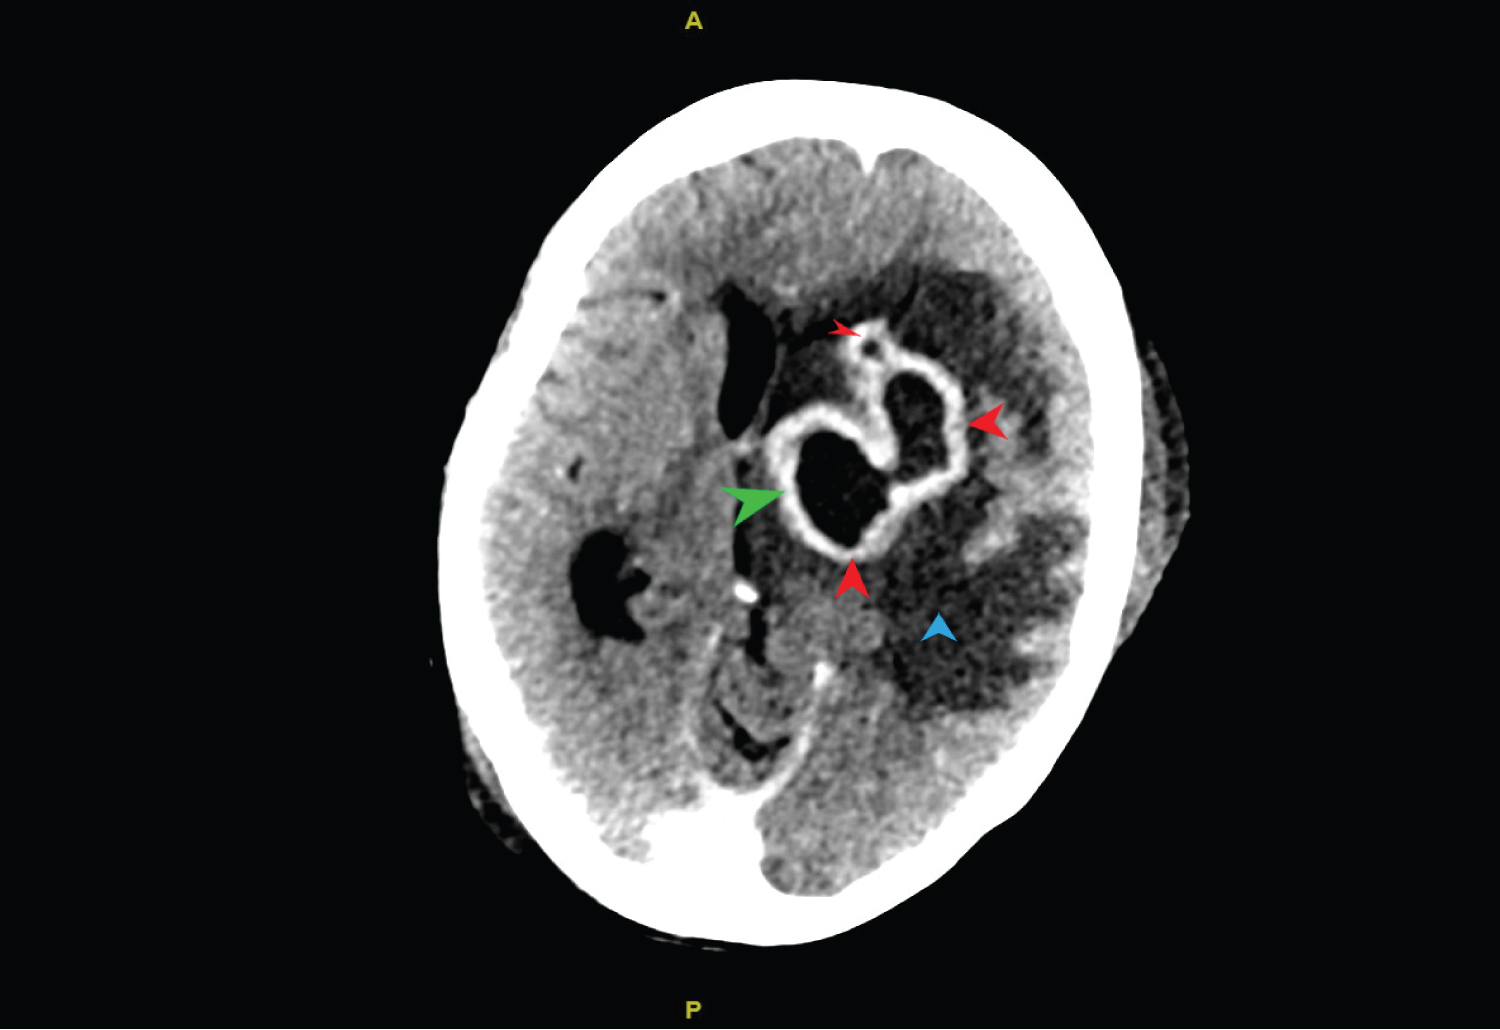

A 33-year-old female was admitted to COVID ICU after testing positive for the disease with 7 days history of fever, cough, inability to open as well as pain in the left eye, and inability to speak with right sided hemiparesis. She was known diabetic and hypertensive. Clinical examination showed presence of multiple pus points in left infratemopral region. Its microscopic examination showed wide area of necrosis along with cluster of mucormycosis. Due to sudden deterioration of patients GCS, CECT head was done (Figure 1) which showed multiple irregular thick walled peripherally enhancing lesion involving the left frontal, parietal and basal ganglia. It also showed presence of significant perilesional edema causing mass effect and midline shift (Figure 1). Patient underwent emergency debridement and burr hole drainage of abscess along with placement of external ventricular drain (Figure 2). The possible mechanism could be that the fungus has gained access to the brain from orbit or paranasal sinus resulting in sequential involvement and abscess formation. Gradually, patient condition deteriorated with progression of disease and she died due to refractory shock and extensive brain involvement.

Figure 2: 3D representation of Skull showing burr hole and external ventricular drain in situ (black arrow).